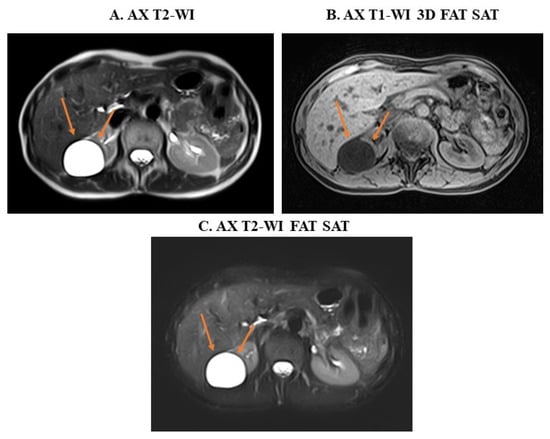

4.2. Monitoring of Abdominal Lesions from CT to MRI